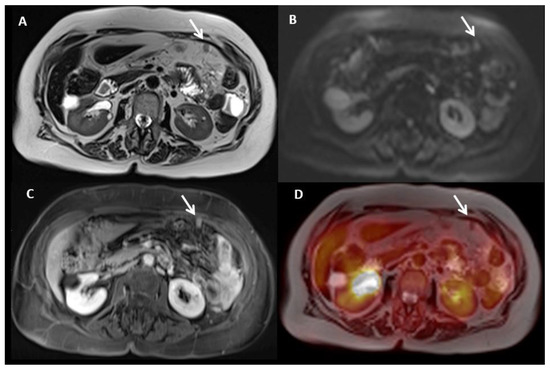

2.2. Magnetic Resonance Imaging (MRI)

6.1. PET/MR